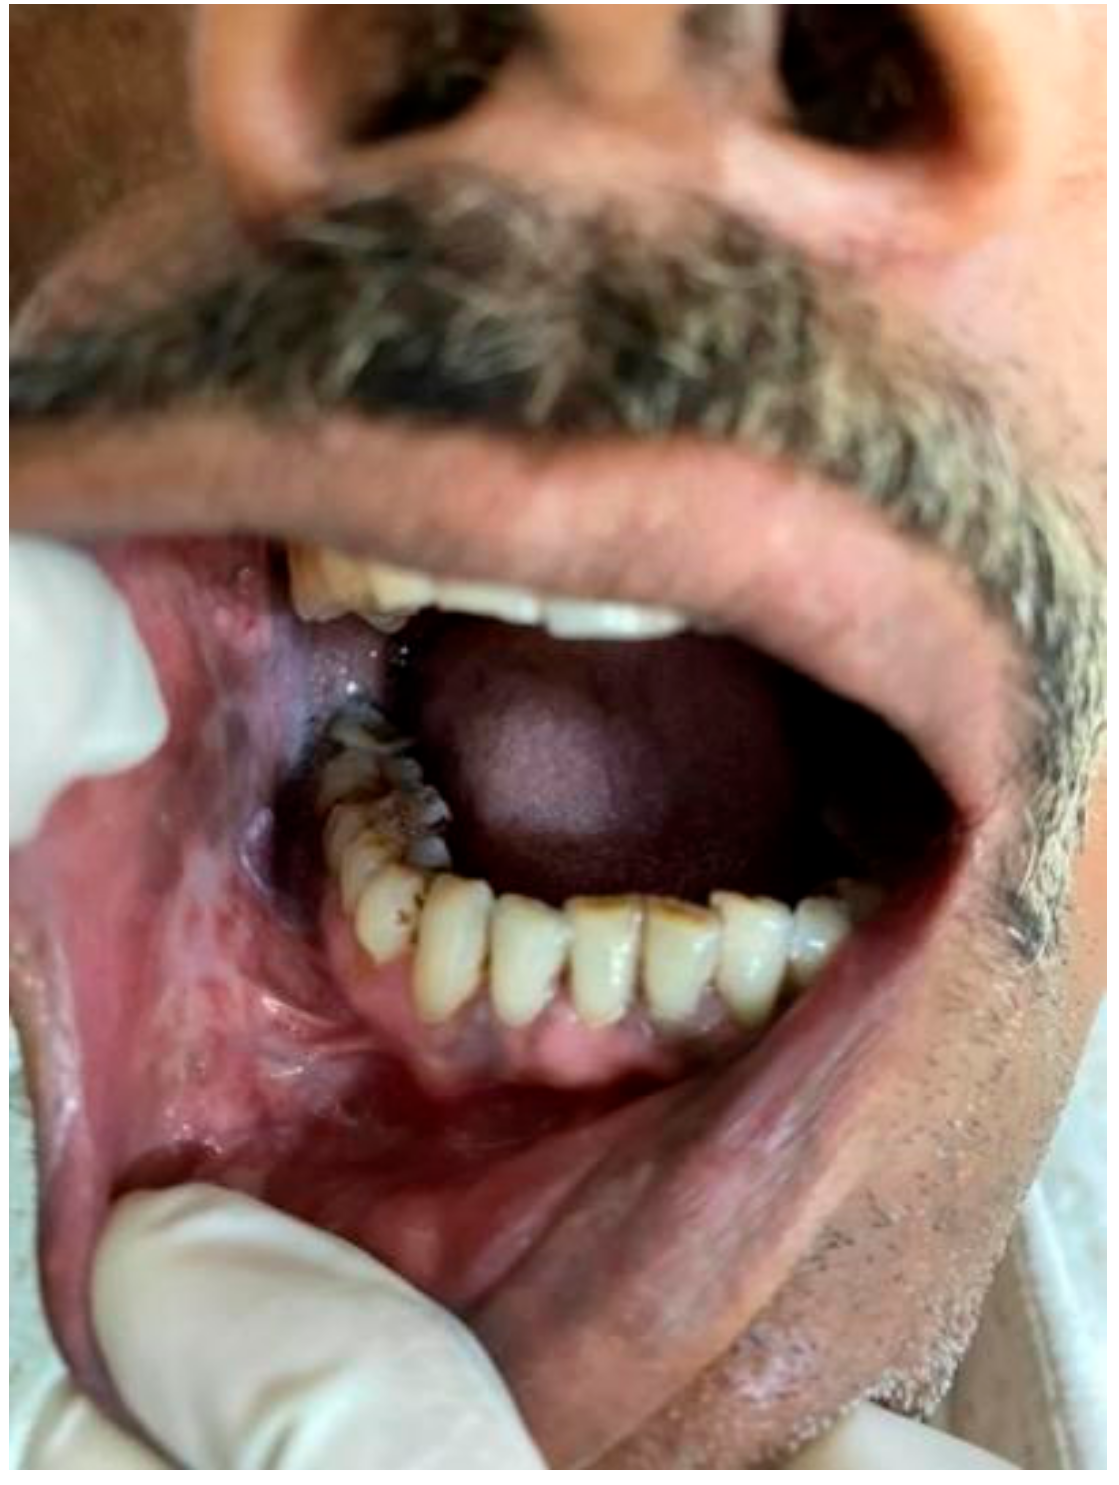

Figure 1. Tobacco user’s lesion on left buccal mucosa leukoplakia.

Figure 2. Tobacco user’s lesion on right buccal mucosa along with oral submucous fibrosis.